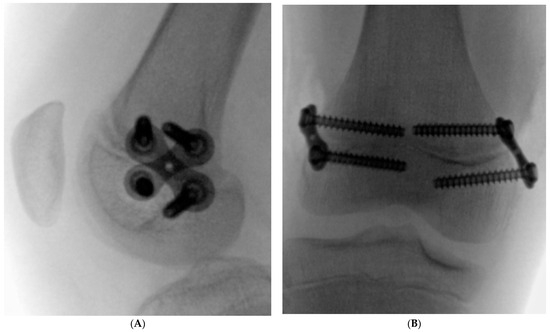

No complications were observed during the treatment or follow-up period, and no coronal or sagittal plane deformities or recurrences of rotational malalignment were reported. No special rehabilitation program was required in the postoperative period. No growth arrest was observed after 8-plate removal. On control radiographs, an open growth plate was visualized, and the distancing of the screw holes from the growth plate after metaphyseal screw removal further confirmed continued growth plate activity (Figure 4).

Figure 4. (A,B) depict lateral radiographs of the knees of two different children, each showing an open growth plate and visible holes from previously placed (and now removed) metaphyseal screws. On follow-up, the holes in both cases have shifted further away from the growth plate, indicating that bone growth remains active in each child.